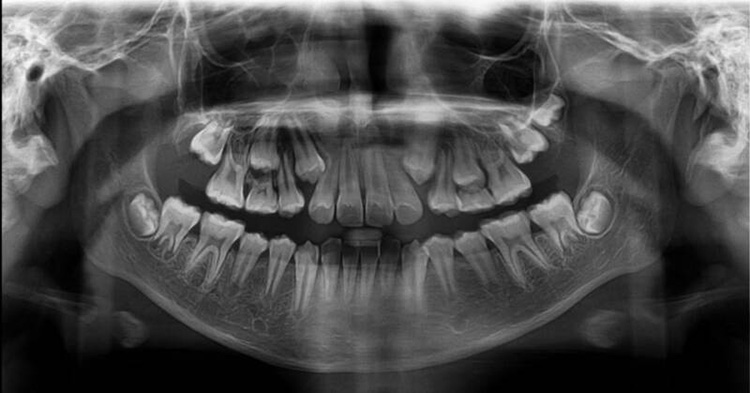

– Chụp X-quang toàn hàm: Bác sĩ dựa vào phim chụp để đánh giá mối tương quan giữa răng, xương hàm, hệ thống dây thần kinh xung quanh. Bên cạnh đó còn xác định tình trạng răng mọc ngầm, răng khôn nếu có để lên phương án điều trị thích hợp.

– Chụp X-quang mặt nghiêng: Bác sĩ phân tích góc độ về răng, xương và mô mềm. Sau đó đánh giá sự tương quan giữa hàm trên và hàm dưới, giữa răng với hàm và cả mối tương quan với xương sọ.

Như bạn đã biết, để đạt được kết quả niềng răng tốt nhất, bác sĩ cần có phác đồ điều trị cụ thể với từng trường hợp khác nhau. Thông qua phim X-quang, bác sĩ hiểu rõ đặc điểm xương hàm, độ sai lệch, độ cứng chắc của răng,… Những điều này nếu chỉ khám thông thường thì không thể phát hiện một cách chính xác. Chỉ khi chụp phim X-quang, hình ảnh truyền tới chân thực, chính xác từ miệng, ngoài mặt, dấu hàm. Bác sĩ dựa vào đó mới đưa ra nhận định đúng về tình trạng răng, hướng dịch chuyển của răng sau khi niềng.

Chụp phim X-quang cũng là một cách để bác sĩ lưu thông tin về tình trạng răng và xương hàm của người niềng răng một cách tốt nhất. Nhờ hình ảnh phim X-quang trước và sau, cả bác sĩ và bệnh nhân đều thấy rõ sự dịch chuyển của từng chiếc răng trong quá trình chỉnh nha. Như vậy, chụp phim X – quang khi niềng răng là chỉ định quan trọng, chỉ định bắt buộc nhằm hỗ trợ bác sĩ tối ưu cho công đoạn về sau.